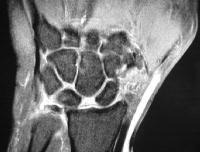

Case 1. Chronic complete scapholunate ligament disruption seen on MRI

Click for larger image